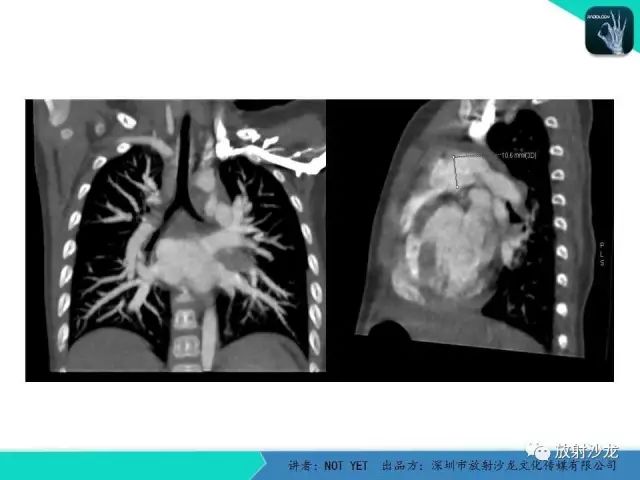

动脉导管未闭1例CT影像表现

【病例】动脉导管未闭1例CT影像表现